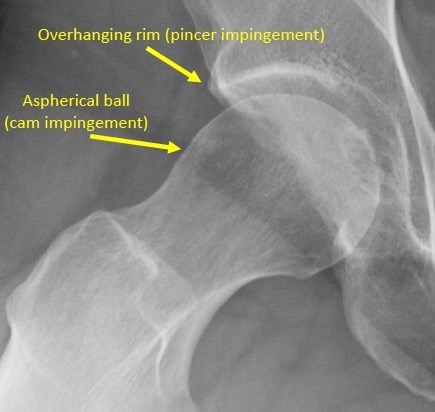

• Femoroacetabular impingement

• 45° or 90° lateral or frog-leg lateral radiographs for femoral head asphericity

• Bony prominence near anterolateral head and neck junction, anterior overcoverage, acetabular retroversion, coxa profunda, protrusion acetabuli

• Femoroacetabular impingement and labral tears

• Groin pain (positive in up to 92% of patients with FAI)

• Positive FADIR (positive in up to 88% of patients with FAI)

• Plain radiographs and MRI arthrogram used for suspected FAI/labral tears